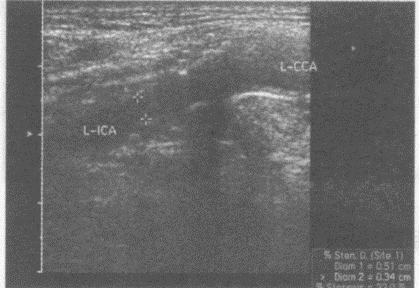

E.骑跨伤狭窄部位多位于后尿道膜部

临床资料:男,79岁,自述夜间如厕时出现一过性眼前发黑、摔倒,急诊入院。患高血压、冠心病十余年。头颅CT:双侧基底结区腔隙性脑梗塞。超声综合描述:双颈总、颈内动脉内膜粗糙,连续中断,中内膜回声强弱不均、增厚,左颈内动脉起始段可见多个中等回声及强回声光团,该段残余管腔内径0.34cm,其远心端管腔内径0.5cm,CDFI:左颈内动脉起始段中等回声及强回声光团区血流充盈缺损,PW:该段V2.06m/s。见下彩图。